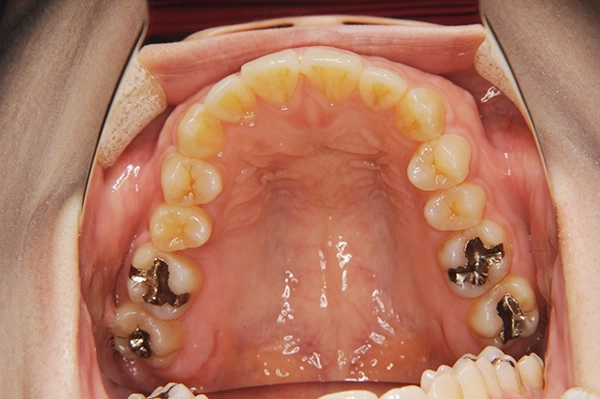

- 年齢/性別

- 30代/女性

- 治療期間

- 3年

- 主訴

- 上下額歯列の凸凹、八重歯

- 治療計画、内容

- 著しくスペースが不足しているため、4本の歯を抜歯、上下顎歯列幅の側方拡大することでスペースを獲得し、歯が安定する位置に並べていく。

- 治療を終えた感想・

治療のリスク

- 犬歯と奥歯を機能させることで安定するかみ合わせを作ることが出来、それに伴い審美的にも改善することができました。かみ合わせが安定したら虫歯の治療をしていく予定です。リスクとしては、歯の移動量が大きいため歯肉退縮を起こす可能性があります。

- 矯正の費用

- 約90万